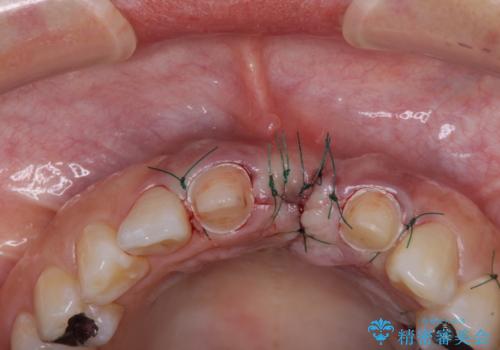

欠損部の歯肉が窪んでいるため、歯肉移植により形態を改善し、オールセラミックブリッジにて補綴することとしました。

- 外科手術のため、術後に痛みや腫れ、違和感を伴います